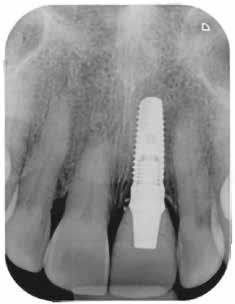

1. kép: A behelyezett implantátum röntgenképe közvetlenül a műtét után… – 2. kép: … és négy hónap gyógyulás után az ideiglenessel

A 64 éves hölgypáciens esztétikus pótlást kívánt 21-es foga helyén, amelyet balesetet követően 2022-ben távolítottak el. Az összes foga egészséges és vitális volt, így a 21-es régióba implantátum került, amelyre cirkónium-dioxid koronát terveztünk. Az implantátum típusát, pozícióját, átmérőjét egyedi anatómiai adottságainak és az adott helyviszonyoknak megfelelően választottuk meg.

Előkezelés

2023 elején került behelyezésre a 21-es régióba egy Camlog Tissue Level implantátum, 4,3 mm átmérővel és 13 mm hosszal. Az eseménymentes gyógyulást követően az implantátum csontosodását a Periotest-eljárással ellenőriztük, majd hagyományos zárt kanalas lenyomatvétel után ideiglenes ellátás készült (2–4. képek).